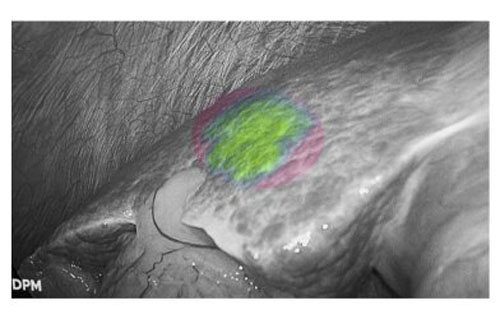

肝癌患者多合并肝硬化背景,而腹腔鏡手術因缺乏觸覺反饋,致使術者在微創條件下難以識別隱匿性病灶。吲哚菁綠(ICG)熒光顯影技術通過術前靜脈注射造影劑,可精準定位3毫米的原發性肝癌和肝轉移癌。該技術有效彌補了腹腔鏡肝膽手術中觸覺反饋缺失的固有缺陷,為微創精準外科提供了重要技術支撐。

熒光顯影技術,可精確顯示肝內隱匿病灶

患者肝右后葉肝癌,根據三維重建精準阻斷右后肝蒂,獲得缺血線后進行熒光反染,顯示肝臟切面的熒光和非熒光界面,助力解剖性肝右后區切除。

三維重建技術直觀呈現肝段劃分及血管、膽管解剖關系,而熒光顯影技術則通過肝段染色,全程顯露段間靜脈,有助于識別肝內肝段間的界限,使肝膽外科醫師可以全程實時觀察肝臟切面變化,及時作出調整,優化手術方案,實現真正意義上的解剖性精準治療。此外,吲哚菁綠(ICG)經膽道排泄的特性使術中膽管結構呈現清晰綠色熒光,大幅提升膽總管辨識度,有效降低腹腔鏡手術中膽管損傷風險,為復雜肝膽手術安全性再添保障,顯著降低了膽管損傷及相關并發癥的發生率,進一步提升了手術安全性。